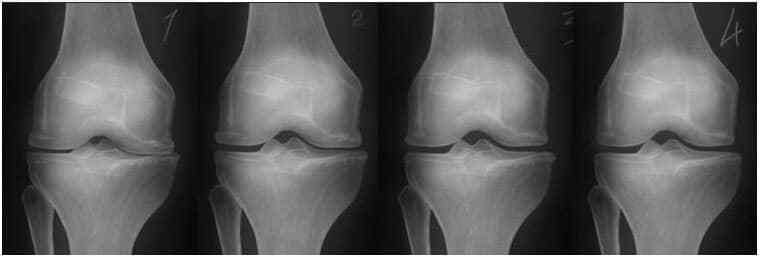

На зображенні нижче показана типова картина відновлення колінного суглоба.